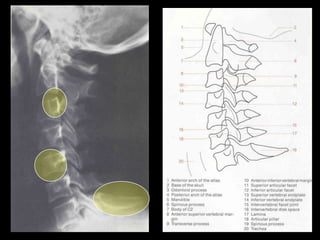

This document provides an overview of normal musculoskeletal imaging. It discusses basic x-ray concepts and densities. It then reviews normal anatomy as seen on x-rays of the skull, spine, pelvis, chest, and extremities. Key anatomical structures are labeled on example x-rays for the shoulder, hip, knee, and foot. Quizzes are included to test recognition of anatomical structures and patient age based on x-rays.